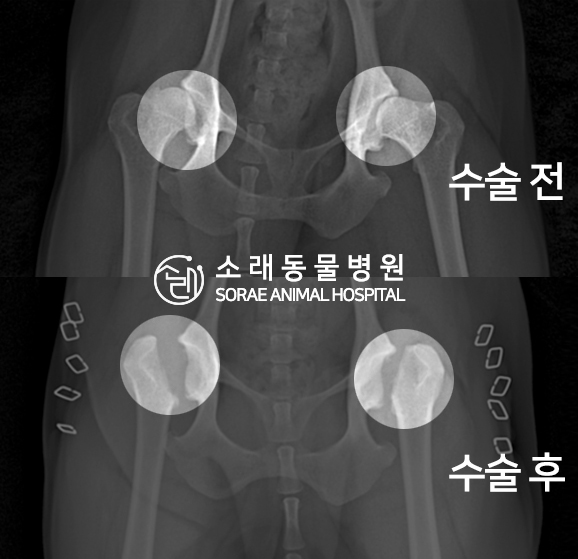

고관절 수술 사례 - #245 포뇨

포뇨는 조금만 걸어도 주저앉는 증상으로 내원하였습니다.

촉진 및 방사선 촬영 결과

대퇴골두 절골술(FHNO) 수술이 필요하다고 판단되었습니다.

문제의 원인이 되는 대퇴골두를 깔끔하게 절단해 주었습니다.

수술 전과 수술 후 촬영한 고관절 방사선 사진입니다.

대퇴골두가 깔끔하게 절단된 것이 확인됩니다.

이제 재활 운동을 통해 체중을 지지할 근육을 키워주게 됩니다.